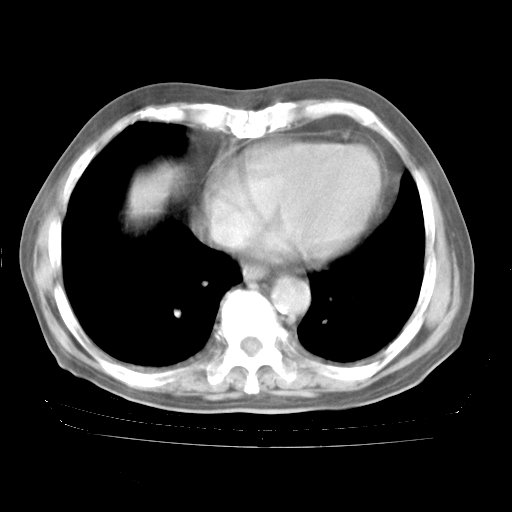

4月28日肺部CT